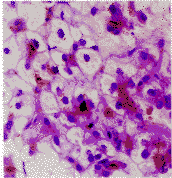

),总胆红素271.78 μmol。L-1,直接胆红素151.5 μmol。L-1。B超及CT示肝及脾轻度增大。行肝脏穿刺活检。病理检查:大体所见为墨绿色线条样组织1条。镜下所见:肝组织结构基本正常,部分肝细胞呈片状气球样变性,体积增大,细胞核小、居中或细胞边缘,有的细胞膜破裂、细胞核消失,部分肝细胞及毛细胆管内见大量粗颗粒状深棕色色素沉积(图1)。肝组织内纤维组织轻度增生形成假小叶样结构,对肝细胞内的深棕色色素颗粒物质进行组织化学染色,黑色素(Masson Fontana银浸法)阴性,胆色素(hall反应法)阳性,脂褐色素(Schmorl反应法)强阳性。病理诊断:Dubin-Johnson综合征。

图1肝细胞呈片状气球样变性,体积增大,核小,部分肝细胞及毛细胆管内见大量的棕黄色色素沉积,假小叶样结构形成。HE×400